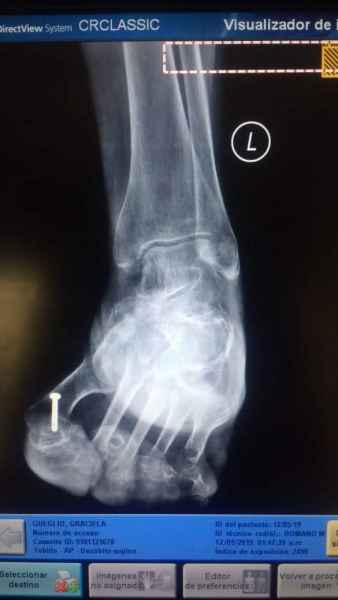

Tanto la estructura del pie como su funcionalismo que es la marcha, pueden ser asiento y manifestación respectivamente de alteraciones locales ó sistémicas, por lo que su cuidadoso examen resulta de extrema utilidad diagnóstica.